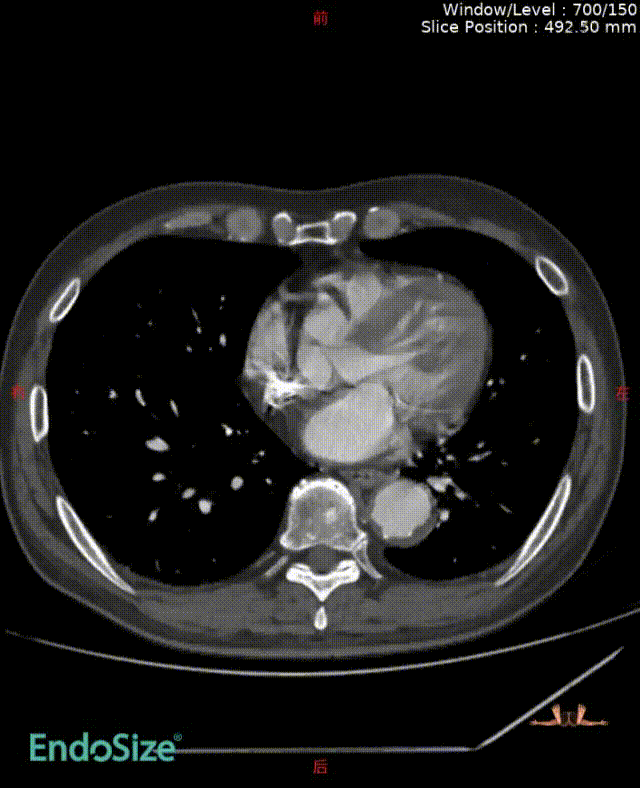

术前情况:74岁男性,肾下腹主动脉瘤,瘤体最大直径66mm,累及双侧髂总,右侧髂内扩张伴开口狭窄,左侧髂内夹层。

手术过程:根据患者及家属要求保双侧髂内,遂计划双侧髂内重建,右侧优先,左侧髂内情况尝试开通。手术中,先进行造影和翻山建立通路。